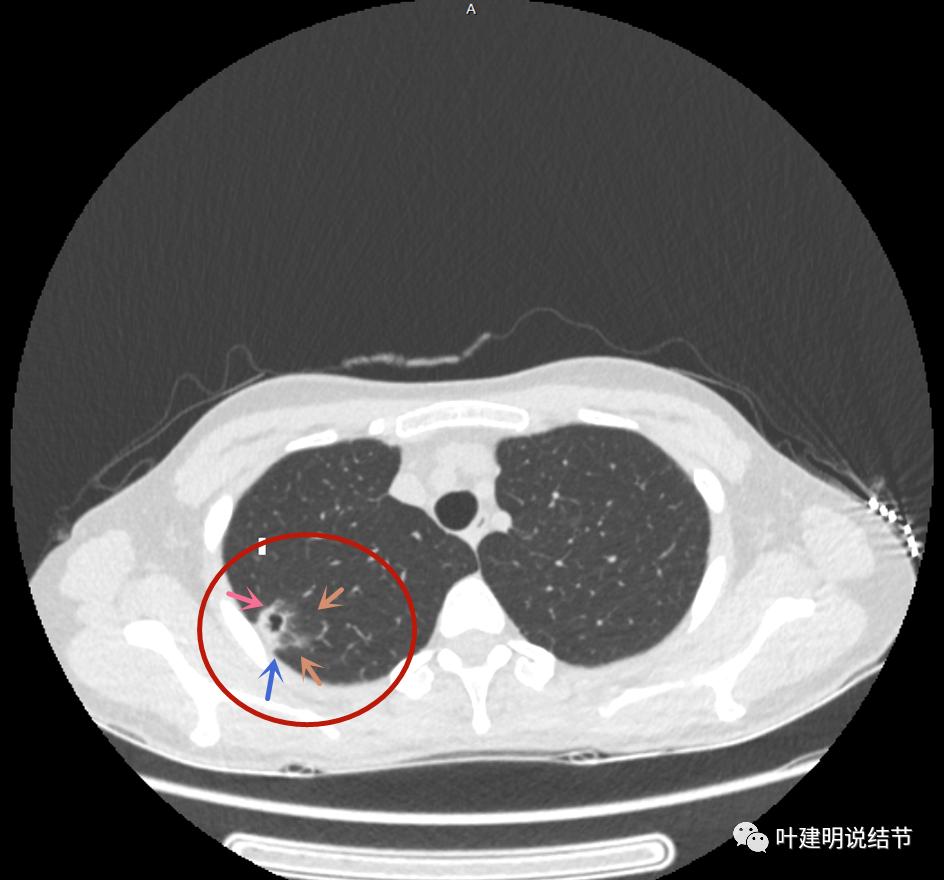

邻近胸膜有增厚(蓝色箭头),主病灶边界较清(红色箭头),实性部分密度过高(粉色箭头),旁边有磨玻璃影,散且模糊(砖色箭头)

邻近胸膜有增厚(蓝色箭头),主病灶实性部分密度过高(粉色箭头),旁边有磨玻璃影,散且模糊(砖色箭头)

邻近胸膜有增厚(蓝色箭头),主病灶实性部分密度过高(粉色箭头),旁边有磨玻璃影,散且模糊(砖色箭头),病灶有空腔(黄色箭头)

主病灶边界较清(红色箭头),实性部分密度过高(粉色箭头),病灶边缘向内凹,缺乏膨胀性(桔色箭头),病灶有空腔(黄色箭头)

邻近胸膜有增厚(蓝色箭头),主病灶的壁密度过高且整个壁密度都高(粉色箭头),旁边有磨玻璃影,散且模糊(砖色箭头)。内壁不均质(此不舒服)